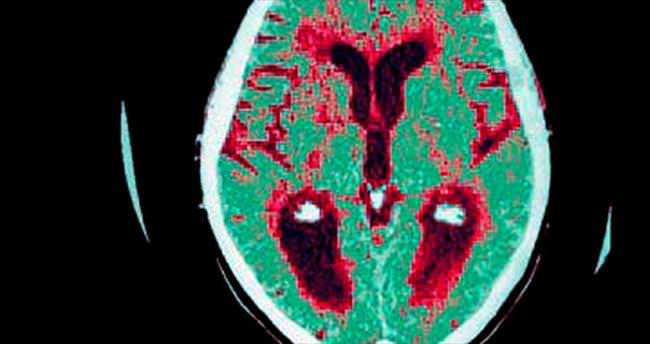

İngiltere’de Cambridge Üniversitesi’nin yaptığı araştırmada, piyasada başka bir hastalığın tedavisinde kullanılan, adları henüz açıklanmayan iki ilacın alzheimer’a karşı etkili olduğu saptandı.

Alzheimer Derneği’nin toplantısında sunulan araştırma, iki yıl önce elde edilen bir bulguya dayandırılıyor. O deneyde farelerin beyin sinyalleri bloke edilerek, alzheimer’a neden olan proteinleri üretmeleri önlenmişti. Ancak protein üretimini durduran ilaç, kilo kaybı ve şeker hastalığı gibi yan etkileri nedeniyle güvenli değildi. Bu iki ilacın ise en az yan etkiyle aynı işlevi gördüğü ortaya çıktı.